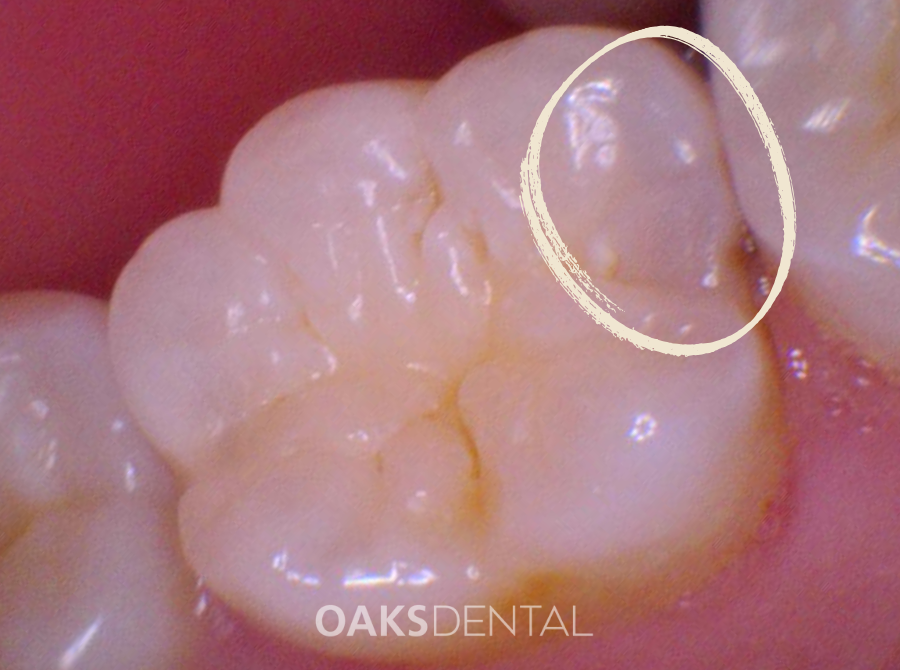

Natural-Looking Results

Our tooth-coloured composite and ceramic materials blend seamlessly with your enamel, restoring both function and aesthetics.

Will my filling be noticeable?

Tooth-coloured fillings are designed to blend with your natural enamel, making them barely visible.